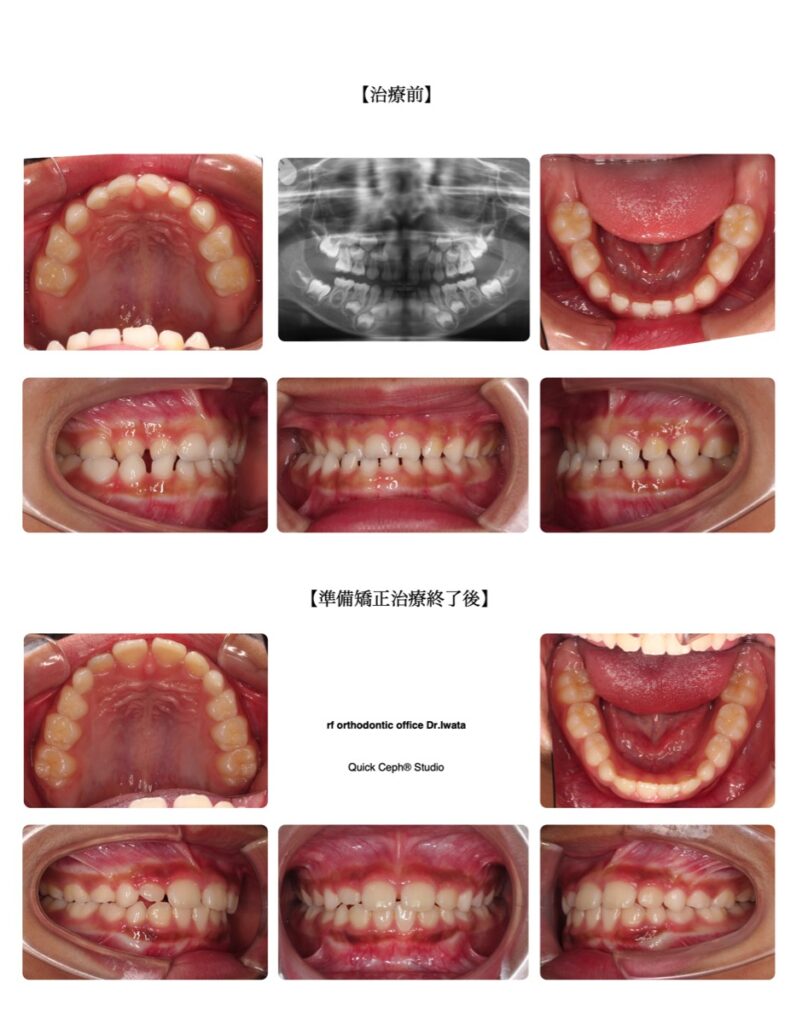

交叉咬合(クロスバイト) 治療症例 2026.04.08 交叉咬合症例 <交叉咬合による下顎の偏位に対する準備矯正治療> 【主訴】右側のかみ合わせが逆になっていて前歯の正中が大きくズレているのを検診で指摘された。今後顎が曲がっていくのが心配なので早めに治療ができれば行いたい。 【主な症状】右側交叉咬合(クロスバイト) 【矯正歯科治療のリスク […]